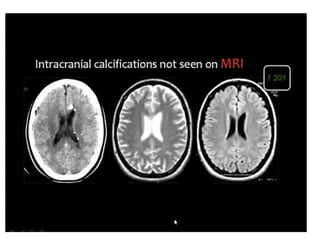

• Imaging

– Plain film – microcephaly with egg shell- like

periventricular calcification

– US/CT/MRI – encephaloclastic lesions, periventricular

ca++, subependymal paraventicular cyst,

ventriculomegaly

– MRI- delayed myelination, encephalomalacia,

migrational disorder (lissencephaly, polymicrogyria,

pachygyria)

1)Congenital CMV is shown with periventricular parenchymal

calcifications , damaged white matter, dysplastic cortex .